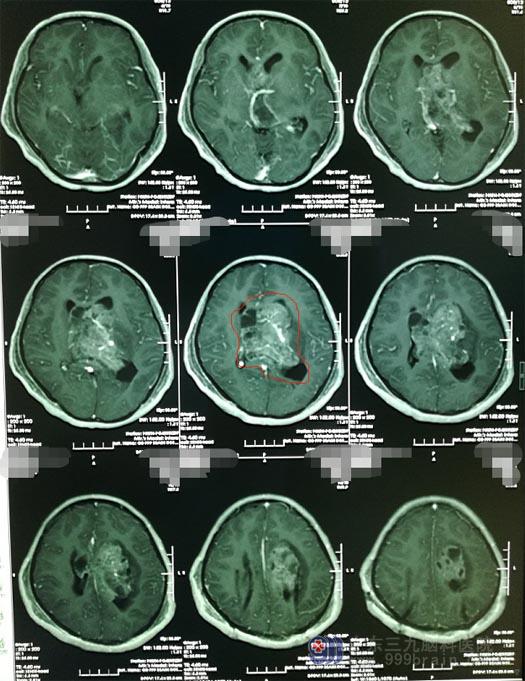

在广东三九脑科医院行头颅MR检查,提示:孟氏孔-双侧侧脑室内占位性病变,大小约7.7cm×5.7cm×5.9cm,考虑中枢神经细胞瘤;头颅CTA示:双侧侧脑室体部巨大占位性病变并出血及钙化,其内血管极其丰富,左侧脉络膜前动脉增粗并供血,伴有粗大引流静脉引流至大脑大静脉。

小云在当地医院已经进行了双侧脑室外引流术。考虑到患者肿瘤巨大,血供丰富,医院副院长、神经外五科主任鲁明建议先行术前放疗,为手术创造有利条件,减少术中出血,提高肿瘤切除程度。急诊放疗后,次日,鲁明带领治疗团队在全麻下行“左侧脑室额角入路左侧脑室及丘脑巨大中枢神经细胞瘤切除术”,术中冰冻结果考虑中枢神经细胞瘤,经过10个小时的奋战,肿瘤被顺利全切。